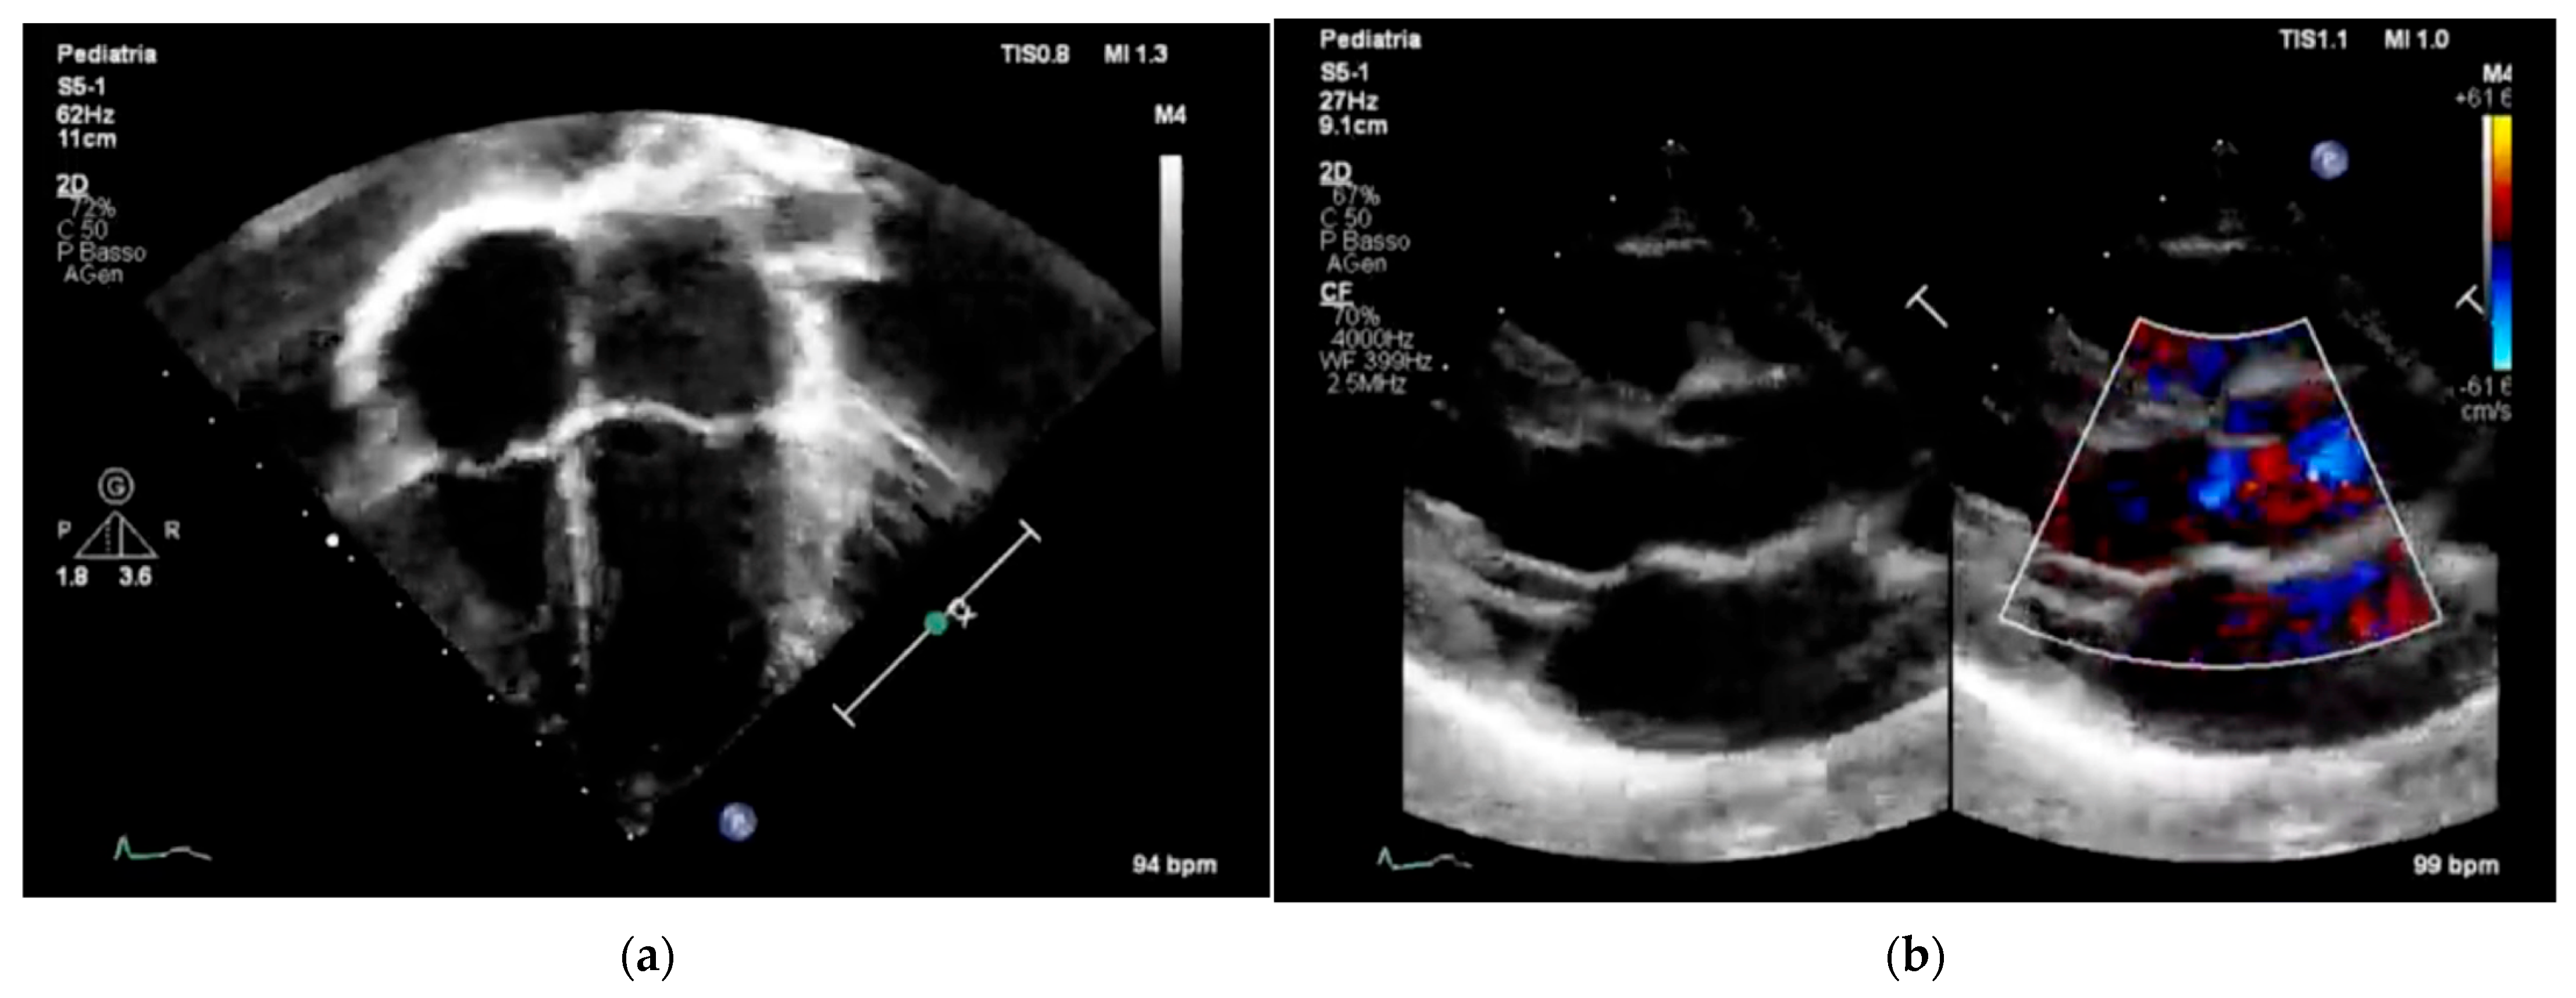

Figure 3 and Figure 4 underscore the importance of age-specific interpretation in pediatric cardiology to distinguish normal developmental findings from true abnormalities.

These representative images highlight the importance of pediatric-specific expertise in interpreting both echocardiograms and electrocardiograms. In children, normal anatomical and electrophysiological features change with age, and misreading them can lead to overdiagnosis or unnecessary restrictions on physical activity. Additionally, including color Doppler imaging in echocardiography (Figure 3b) emphasizes the importance of evaluating hemodynamic function alongside structural integrity, especially in screening protocols designed for early detection of CHD [7] or functional issues. Similarly, the ECG patterns shown in Figure 4b display the typical pattern of physiological T-wave inversion in the right precordial leads (V1–V3), which is common in children under 8 years old. This underscores the need for age-specific ECG interpretation criteria to prevent normal variants from being mistaken for pathological conditions.

Overall, Figure 3 and Figure 4 emphasize the importance of combining imaging and electrophysiological tools in pediatric cardiovascular screening while also highlighting the crucial role of age-specific norms and clinical context in ensuring accurate, efficient, and cost-effective screening results.

Figure 4. Two representative examples of electrocardiography in pediatric subjects: (a) normal pediatric 12-lead electrocardiogram; (b) sinus arrhythmia and negative T waves in leads V1–V3 as a normal finding in 3-year-old children.